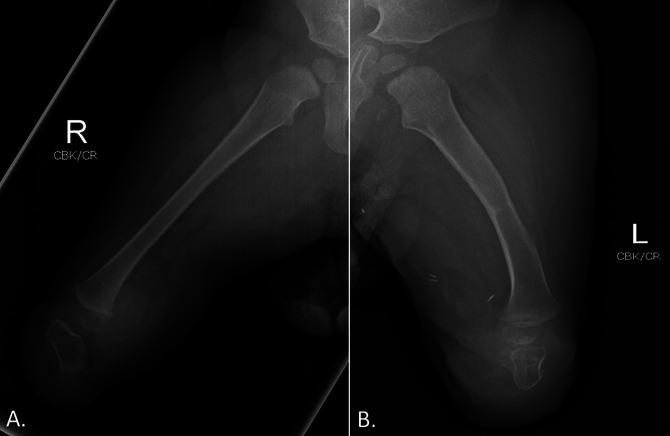

Tibial deficiency (also known as tibial hemimelia) is a rare condition with variable presentation. A 2-month-old patient presented with absent bilateral tibias. When the patient was 1 year, a novel reconstructive surgery was done. A bilateral fibular resection with pedicled calcaneus transfer was done, allowing for transfer of the calcaneus along with the overlying glabrous skin and soft tissues to the end of the femur. The patient was permitted to weight-bear after the 4-week postoperative follow-up. At the six-month follow-up, the patient was able to pull to stand and walk with assistance without any reports of pain.

胫骨发育不全(也称为胫骨半肢畸形)是一种罕见的疾病,表现多样。一名 2 个月大的患儿双侧胫骨缺失。患儿 1 岁时,接受了一种新的重建手术。进行了双侧腓骨切除和带蒂跟骨转移,将跟骨连同其上方的无毛皮肤和软组织转移到股骨末端。术后 4 周随访时,患儿开始负重。在 6 个月的随访中,患儿能够在辅助下拉站和行走,没有任何疼痛报告。